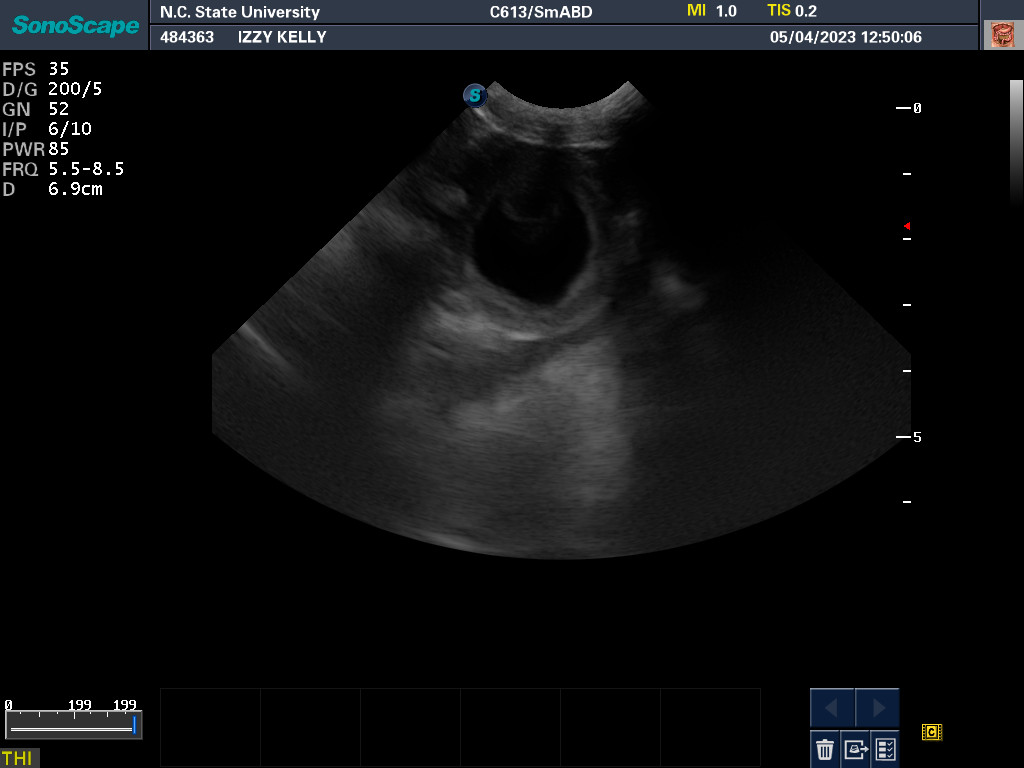

NC State University for an autopsy.